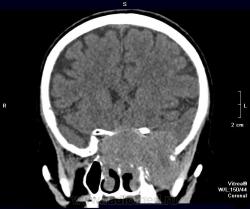

Краниофарингеома? Есть ли данные контрастирования?

Нет, контрастирования не делали. Бабушку отпустили домой, сказали, что опухоль неоперабельная. Вряд ли это краниофарингиома. Скорее это опухоль из основной пазухи или из решеток. У нас она прошла как опухоль основания черепа. Увы!